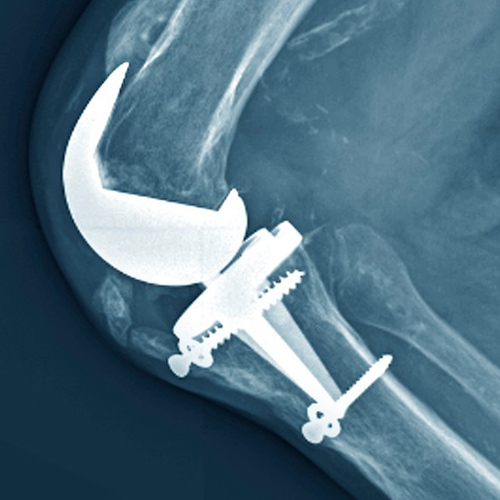

X-ray, CT/MRI 등의 정밀 검사를 통해 손상된 관절의 상태와 다리 축 변형 정도를 정확하게 진단합니다. 로봇 또는 컴퓨터 내비게이션 수술을 할 경우, 이 데이터를 기반으로 인공관절의 최적 크기, 위치, 각도를 미리 설정하고 가상 시뮬레이션을 통해 수술 계획을 완성합니다.

절제된 뼈의 표면에 맞추어 금속 및 특수 플라스틱 재질로 구성된 **인공관절 구성품(임플란트)**을 삽입하고 단단하게 고정합니다.

(환자 상태에 따라 시멘트나 무시멘트 방식을 적용합니다.)

삽입된 인공관절이 정확한 위치와 각도에 있는지, 그리고 무릎의 움직임(굴곡/신전) 시 인대와 주변 조직의 균형이 잘 맞는지 최종적으로 확인하고 조정합니다.